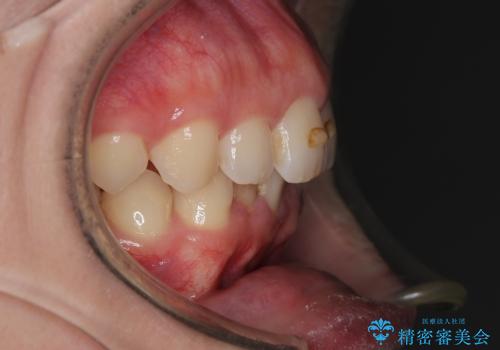

右側臼歯部の咬合改善のために、臼歯部のみ部分的なワイヤー矯正を行い、咬合改善がみられてからインビザラインにて全体的な矯正を行なっていく治療計画を立てました。

噛み合わせをよくするために、ワイヤー矯正とインビザライン矯正のどちらの期間も必要な箇所にゴム掛けを行いながら治療を行いました。